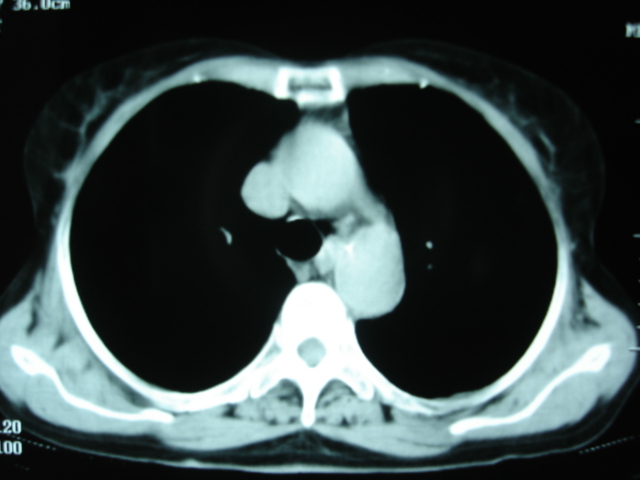

以下是引用卜一在2009-9-7 19:51:00的发言:[br][br] 1 左侧胸内甲状腺占位-多考虑甲状腺腺瘤! 2、左肺门占位-建议增强扫描以便明确性质。 3 慢支并感染! [br]

以下是引用shibing在2009-9-7 20:40:00的发言:[br]左侧胸内甲状腺占位-多考虑甲状腺腺瘤! 2、左肺门占位-建议增强扫描以便明确性质。 3 慢支并感染! [br]